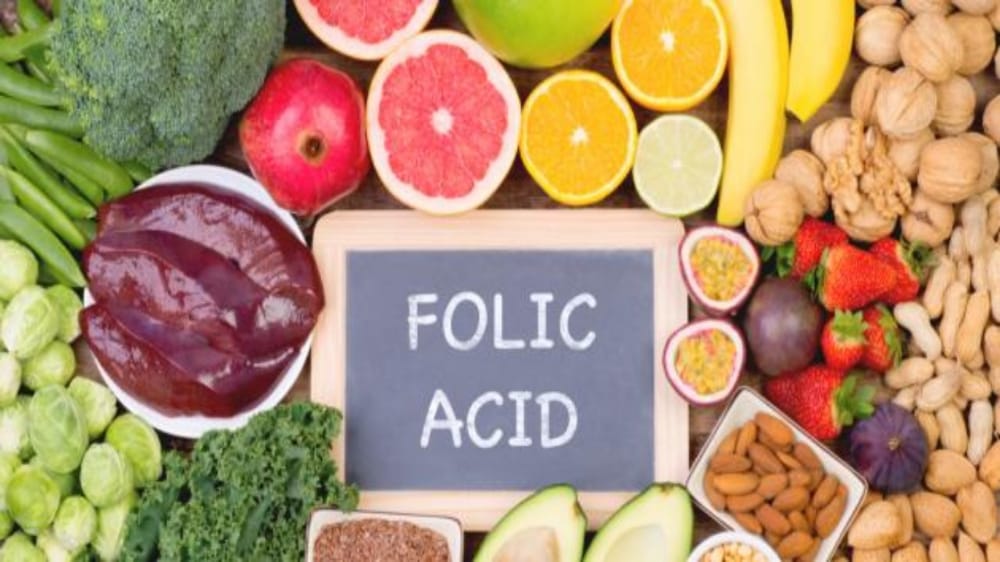

“فهد الطبية” توضح مصادر حصول الجسم على حمض الفوليك